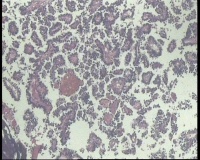

| 性别 | 女 | 年龄 | 53岁 | 临床诊断 | 右侧卵巢囊肿 |

| 一般病史 | 彩超:盆腔可见囊实性回声,囊性为主,大小约5.0x3.7厘米,其内可见分隔回声,部分分隔内回声不纯净,形态欠规整 | ||||

| 标本名称 | 腔镜下右侧卵巢囊肿手术 | ||||

| 大体所见 | 囊壁样组织5.5x5.0厘米,4.5x2.5厘米2块,壁厚0.1-0.2lm,囊壁大部分光滑,局灶见0.7x0.5x0.3厘米淡黄色突起组织,另见淡黄色、肉粉色质软组织2.8厘米一堆。 | ||||